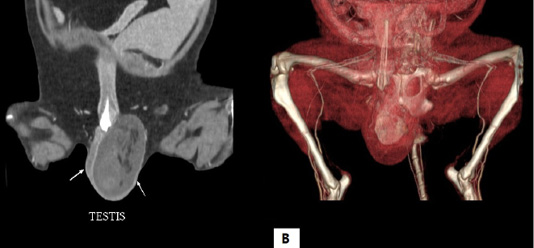

Computed tomography scan of the testicle. (A) Two-dimensional computed tomography scan shows hyperdensity of left testicle and (B) three-dimensional computed tomography scan presents a mass within the left testicle.